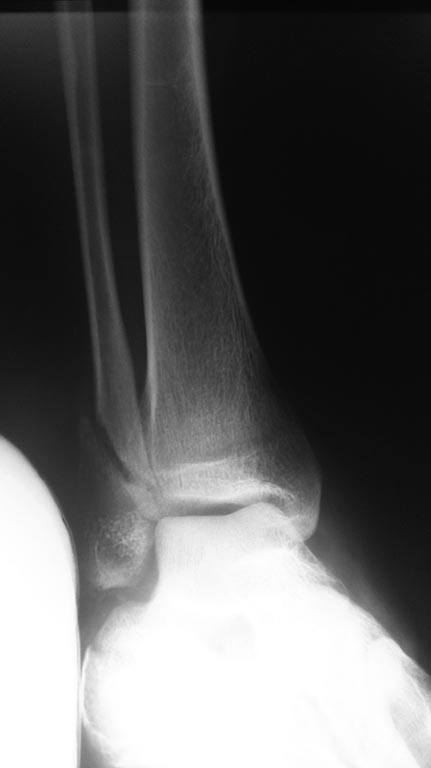

Больной Х. Упал с высоты 5го этажаЗак.пер L1 з.пер локт отростка. Перед.

Задн колоны таза. Подвертельный пер. Пр бедра. ОСКОЛТЧАТЫЙ ПЕРЕЛОМ ОБОИХ

ПЯТОЧНОЙ КОСТИ +н.лодыж лева

Сделано: Таз фиксирован АВФ. Ск вытяжение чз буг б.берцовой кости справа

. лева н.конеч фиксирован шиной. Планируем DHS пр бедра. Пятку спицами

Какой метод эффективный в данном переломе пяточной кости????? Спасибо (